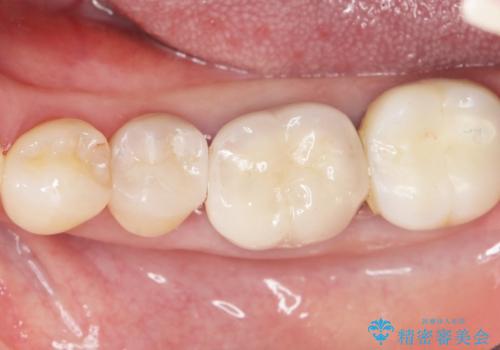

古い詰め物とう蝕を除去し、審美的で適合が良く二次う蝕になりにくいセラミックインレーによる修復を行いました。

審美的な仕上がりと自然な咬み心地に喜んで下さいました。

インレーの種類:セラミックインレー(e-max press)